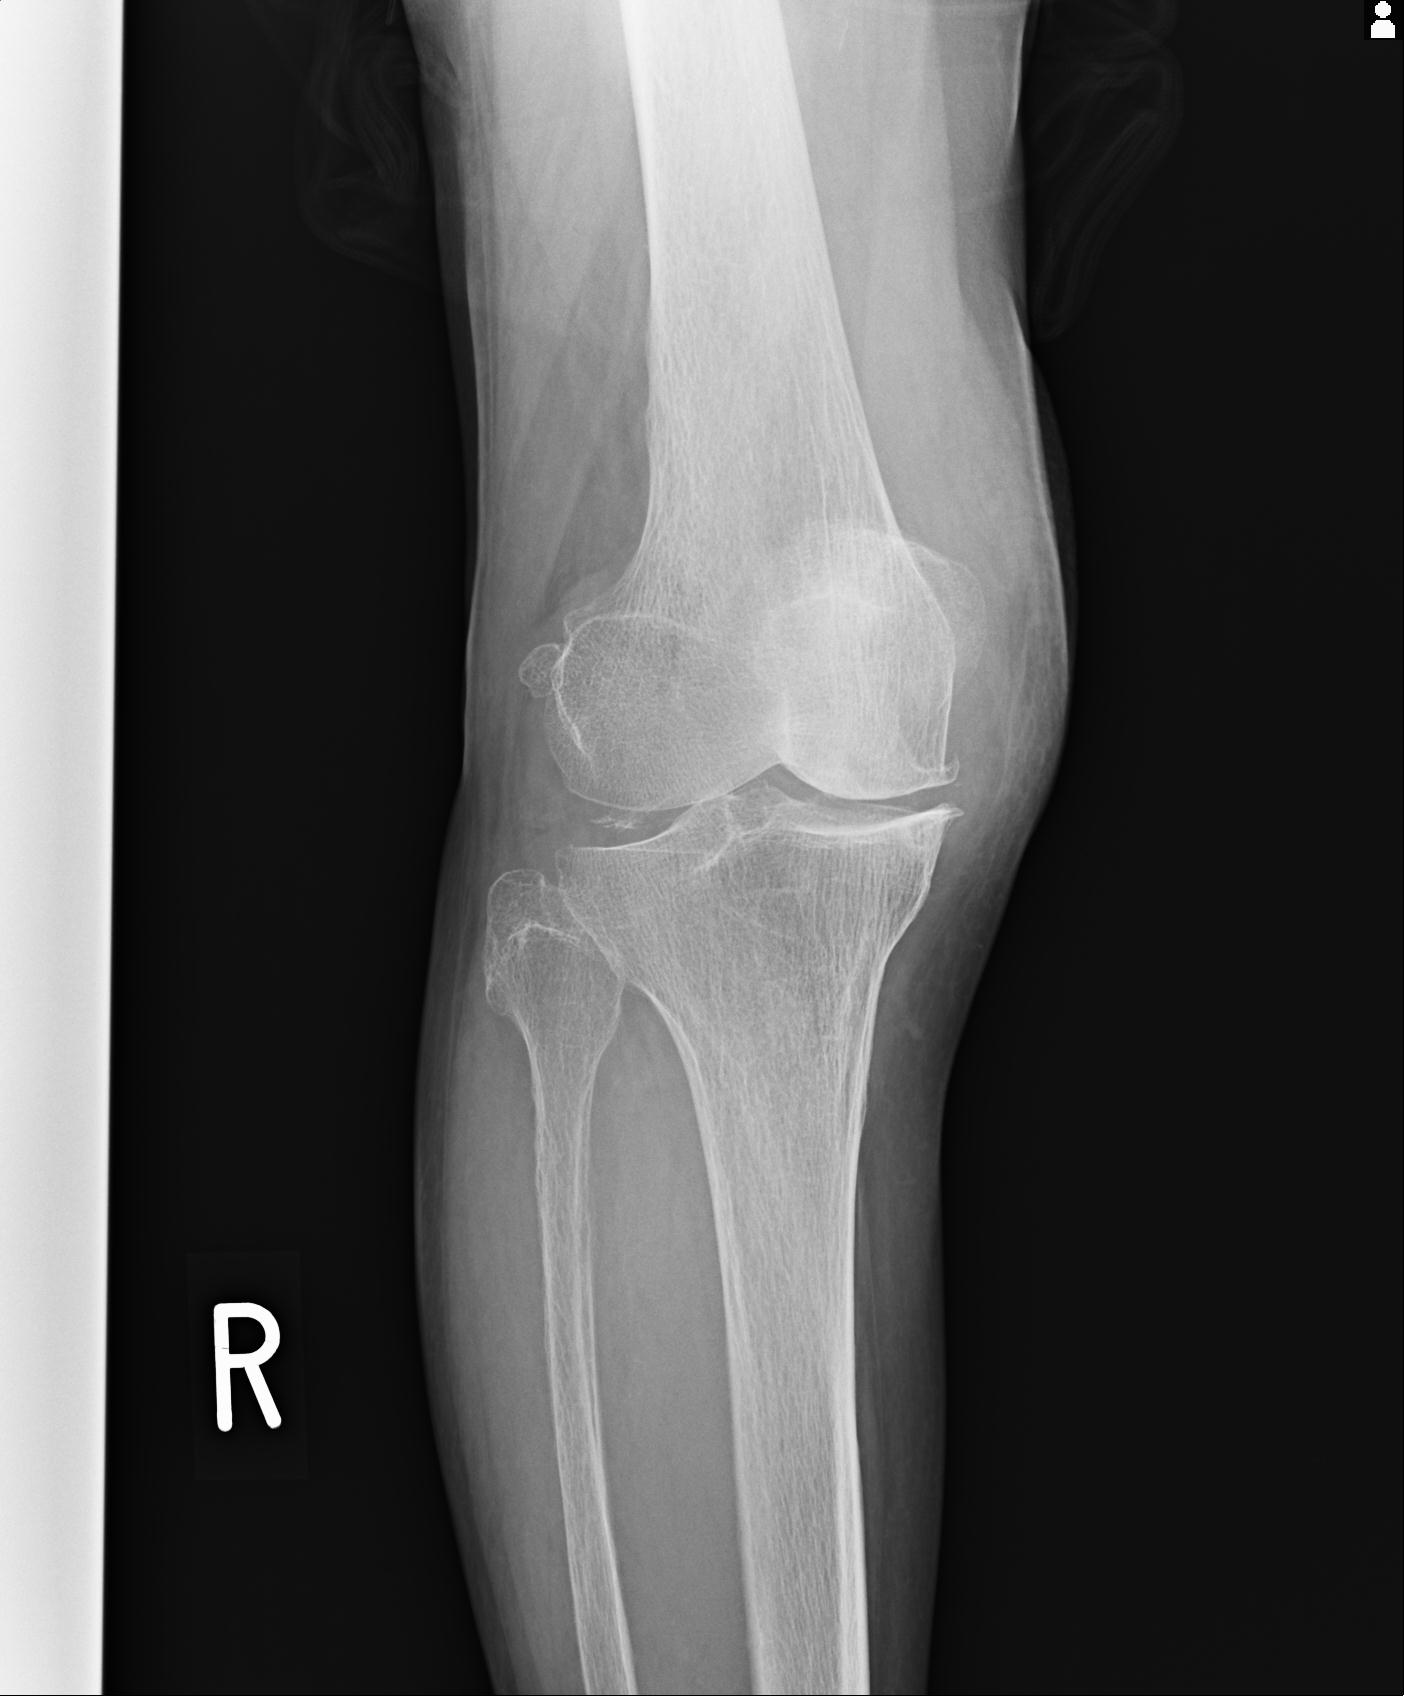

49554 3/13 膝 4R 3/16 4R 1/18 2R 78歳男性 膝蓋骨骨折